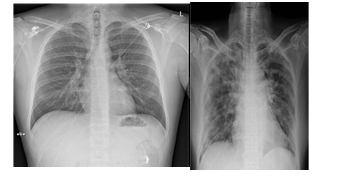

Figure 1Coronavirus and pro physician chest X-ray pictures Figure 2Coronavirus and Non Corona virus adolescents' chest Tomography pictures

According to the Centers for Disease Control and Planning, Even if a chest CT or X-ray shows COVID-19, its only definitive technique of diagnostic is the viral screening (CDC). And endeavor is the first step in creating a tool that verifies or provides further details regarding the present disease through viral investigation. The greatest result to have is achieved by VGG-19 (spatial Geography Group), which classifies pulmonary symptoms with a highest score of 100 percent. The normal class did well, though the COVID-19 classes have had minor issues. Categorization issues despite strong results. So far, in the COVID-19 class, this model has produced the greatest and most regular outcomes.